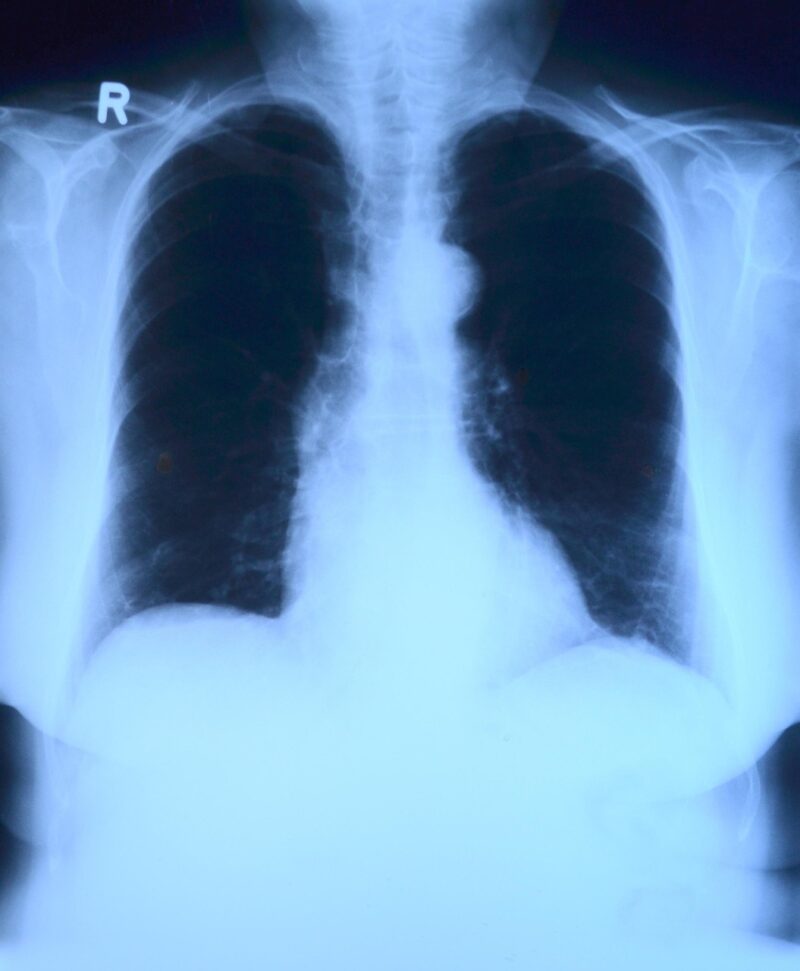

Ejemplo de una imagen de radiografía de tórax disponible en el conjunto de datos: a) imagen original, b) imagen original con las costillas etiquetadas en colores.